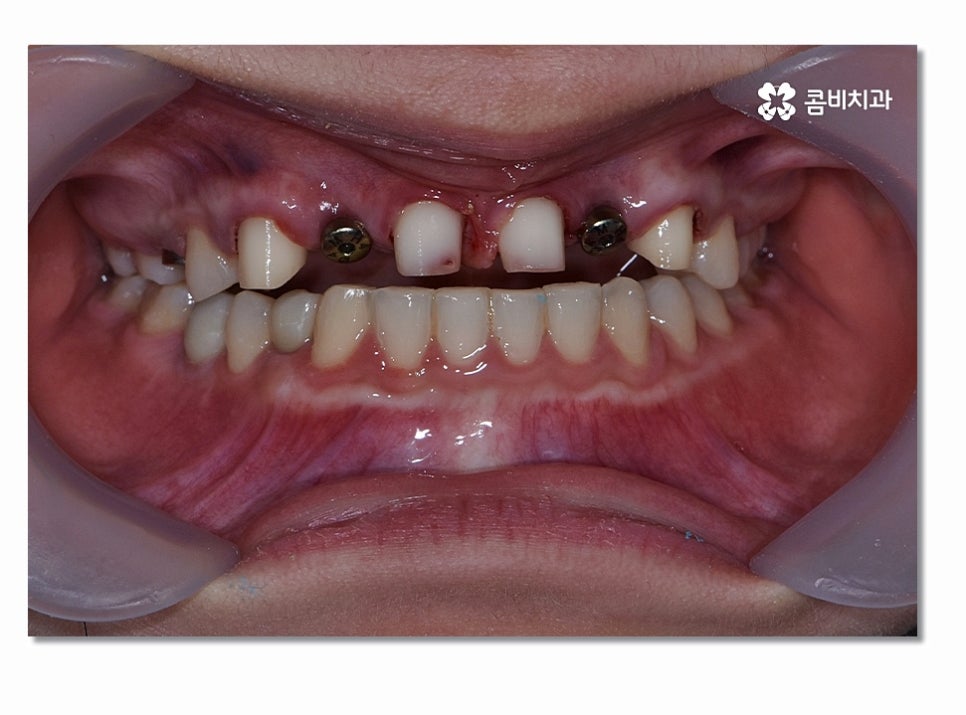

특히 위 환자분의 경우에는 앞니 올 세라믹 치료와

치아교정, 임플란트를 동시에 진행해야 했기 때문에

앞니임플란트와 함께 주변 치아가 심미적으로

자연스럽게 어울리면서 교합까지 잘 체크해야 했기 때문에

유독 여러 측면에서 섬세한 치료가 필요했다고 볼 수 있어요.

앞니임플란트 시술 후에는 보철물에 과도한 힘이

가해지거나 끈적이고 질긴 음식은 피하시는 것이 좋으며

특히 앞니임플란트 치료 후에는 잇몸질환으로 인해서

임플란트 주위염이나 잇몸질환으로 인한 잇몸의 흡수를

주의해야 하는데 앞니는 잇몸이 얇고 한 번 흡수된

잇몸은 다시 회복시키기 어렵기 때문에 잇몸질환에 특히

주의하시고 칫솔질과 함께 치실 사용을 필수적으로 권장하고 있어요.